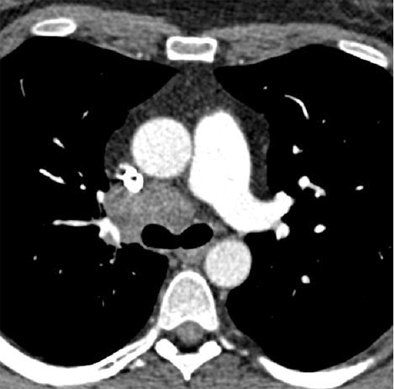

The group from Lille, France compared standard-dose filtered back projection (FBP) to low-Kv imaging with the SAFIRE algorithm in patients referred for follow-up chest CT; as a result all patients had a baseline CT scan at normal dose for comparison.

Iterative reconstruction offers a chance to provide high-quality images from low-dose datasets, said Dr. Julien Pagniez, from the department of thoracic imaging at Hôpital Calmette. "The purpose of our study was to compare the quality of CT angiography with 50% dose reduction using the raw-data-based iterative reconstruction algorithm SAFIRE by Siemens in comparison with standard filtered back-projection images," he noted.

"In daily practice, we set kilovoltage according to the body weight," said lead investigator Dr. Martine Rémy-Jardin, also from Lille. "Then for the follow-up there was a 20% kV reduction and we had to adapt the mAs because we reduced the kilovoltage, and it was done to obtain an overall 50% dose reduction ... What we wanted to test was the ability to restore image quality with iterative reconstruction."

The 80 consecutive patients undergoing follow-up chest CT scans all had their second examinations acquired in a manner similar to the first scan, except that kV was reduced by 20% in the second scan to produce a 50% reduction in CT Dose Index Volume (CTDIvol). SAFIRE was used to reconstruct the images in the low-dose scan, Pagniez said.

In both sets of images, the authors obtained objective noise measurements by measuring the standard deviation of XL values in regions of interest in mediastinal images at two anatomic levels -- the tracheal lumen and the descending aorta -- and signal-to-noise ratios were calculated from these levels. In addition, the visual appearance of noise was rated as minimal, moderate, or severe, and the overall image quality was evaluated subjectively.

"There was an immediate reduction of 52.8% in the dose-length product," between the baseline T1 exam (163.6 mGy cm) and the follow-up T2 scan (77.3 mGy cm), Pagniez said. The results also showed significantly less objective noise in the trachea in mediastinal (T2: 18.33 ±5.89; T1: 21.48 ±9.41) (p < 0.0001) and the lung images (T2: 41.28±10.39; T1: 49.77±11.73) (p < 0.0001).

The low-dose protocol also demonstrated significantly higher signal-to-noise (T2: 12.92±3.80; T1: 10.86±3.15) and contrast-to-noise (T1: 11.68±3.64; T1: 9.42±3.13) ratios (p < 0.0001).

Finally, in subjective evaluations of image quality, the two thoracic radiologists evaluating the images found similar visual perception of noise on mediastinal (p = 0.1317) and lung images (p = 0.3657), mainly rated as moderate; and (d) similar overall image quality, rated as excellent in 23 % (18/80) (versus T1: 21/80; 26%) and good in 77 % (62/80) (T1: 59/80; 74%) of CT exams (p = 0.4054).

Overall image quality between the normal-dose and low-dose SAFIRE images was rated excellent in 23% of the cases, (18/80) (versus T1: 21/80; 26%), and good in 77% of cases (T1: 59/80; 74%) of CT examinations (p=0.4054), the group reported.

"Despite the dose reduction, there was a significant reduction in objective noise at the level of the trachea on both mediastinal and lung images on the follow-up lung images with low kV and iterative reconstruction," Pagniez said. "There was no significant difference in objective noise between the two groups at the level of the aorta on mediastinal images. The signal-to-noise and contrast-to-noise ratios were significantly improved at T2."

The technique provided equivalent image quality compared to low kV chest CT angiograms at a 50% dose reduction, according to Pagniez. "This suggests the possibility for reduced dose while improving vascular enhancement on low-dose chest CT exams in routine clinical practice."